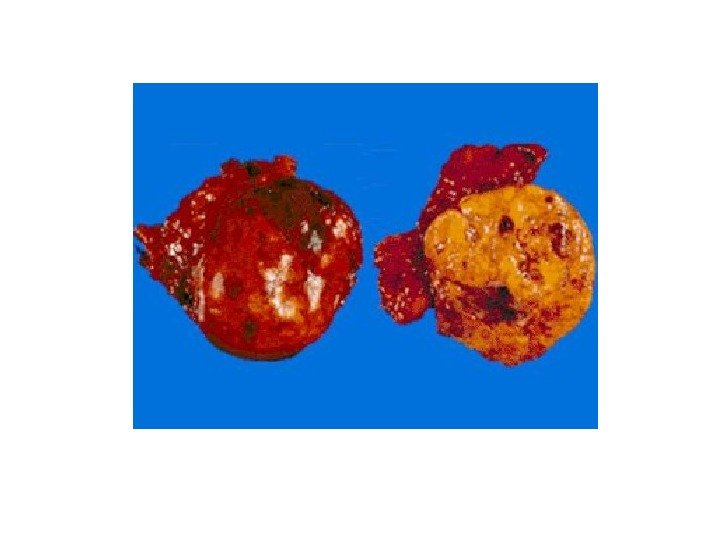

ФЕОХРОМОЦИТОМА

ФЕОХРОМОЦИТОМА